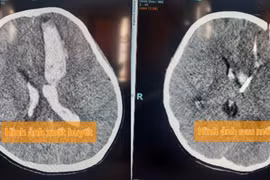

Nam thanh niên 25 tuổi được đưa vào cấp cứu trong tình trạng hôn mê, bất tỉnh, liệt nửa người. Bác sĩ chẩn đoán anh bị đột quỵ, tiên lượng nặng. Nam thanh niên này có tiền sử khỏe mạnh nhưng mỗi ngày hút 20 điếu thuốc.

(khoahocdoisong.vn) - Bệnh nhân H.T.D.H. (29 tuổi, quận Bình Tân, TPHCM) bị xuất huyết não do dị dạng động tĩnh mạch não. Cách đó 6 tháng, ông ngoại của chị H. cũng phải nhập viện cấp cứu vì lý do tương tự.